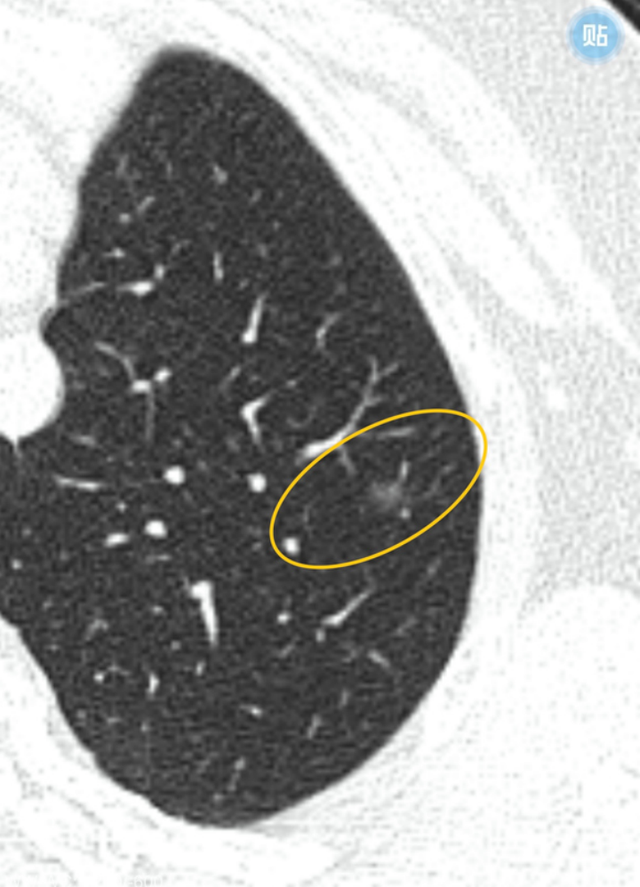

混合磨玻璃结节,伴有胸膜牵拉——肺腺癌

图片尺寸1888x1422